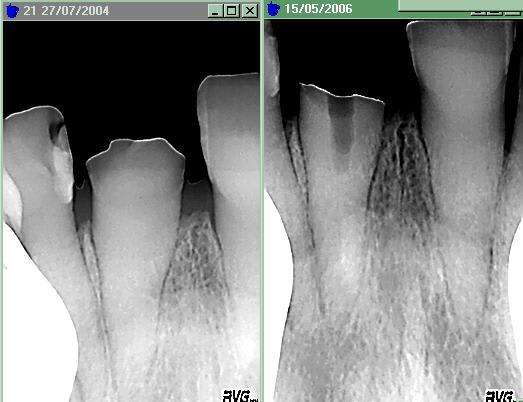

Puisque l'on parle de canal calcifié : aujourd'hui même : dent cassée nette à la gencive. Bien obliger d'essayer de forer pour mettre un tenon. ( à noter qu'il n'est pas facile de forer pile dans l'axe ! ). Legere sensibilité au forage, tien, tien. A force de chercher un peu, j'ai trouvé le point sensible, puis terminé sous anesthésie.

Calcifié1 cnbzzw - Eugenol

Calcifié2 hwsb6c - Eugenol

Sur que cela fait plaisir. J'ai surtout eu peur de ne pas trouver le canal, alors que la dent était sensible au forage. Dans ce cas, je crois que j'aurai déposé un peu de MTA au fond avant reconstruire.

Je pense que si j'avais anesthésié directement, je ne l'aurai sans doute pas trouvé l'entrée, malgrés loupe et fibre optique.

Enfin, heureusement, c'était un RV de 2 h prévu, car il m'a fallu 1h 3/4 pour l'endo et la provisoire.